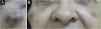

Hematoma and ecchymosisThese are the most common adverse effects after the application of BT. Ecchymosis occurs more frequently than hematoma, which is rarer but can occur after applications even with fine needles and a sharp bevel5,8 (Fig. 1).

To treat hematomas, analgesics, heparinoid creams, and Arnica montana can be administered, although there is no scientific evidence.8,9 The patient should be instructed on the decomposition and absorption of the extravasated blood.